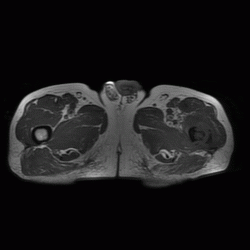

Патология костной структуры. Динамика. Ваше мнение?

Из анамнеза: 6 мес назад была травма. Не обращался,не лечился. Боли сохранялсиь,в последнее время усиливаются.

cпециалист по МРТ выставляет остеомиелит. направлен на открытую трепанбиопсию.Буде информация-сообщу.

Биопсия это единственно правильно, на мой взгляд, больше данных за онкологию, но здесь обширный ряд: от той же саркомы Юинга (остеосаркомы, ЗФГ) до мтс, т.е имеет место некий весьма агрессивный процесс в виде остеолитической деструкции, инфильтрации кости. М.б. и поднадкостничная гематома, осложнившаяся остеомиелитом, но за полгода воспалительный процесс должен был как-то себя проявить...

Мне кажется, уже по первому снимку можно было онкологию выставлять.